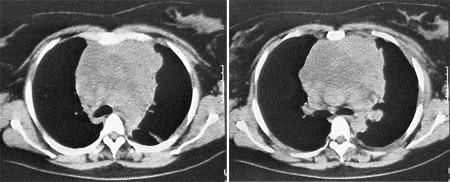

2962. Учитывая локализацию тератобластомы средостения по данным томографического среза,

с целью её удаления, целесообразно использование